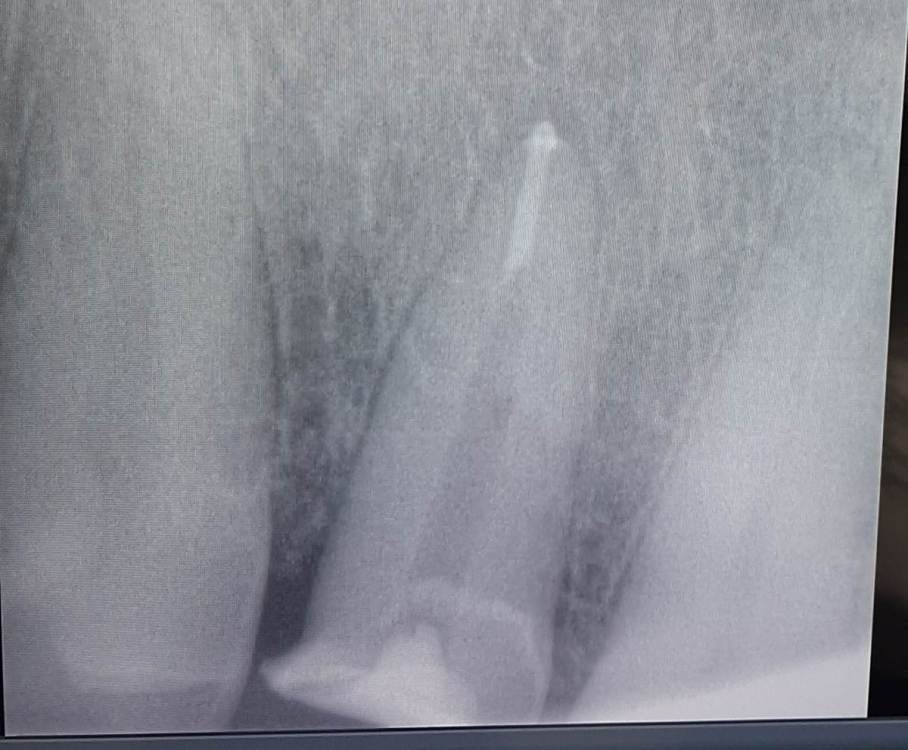

GENRY Опубликовано 19 августа, 2023 Поделиться Опубликовано 19 августа, 2023 (изменено) Всем добрый день! Неделю назад произошел скол нижней части цирконивой коронки 12 зуба с внутренней стороны. Коронке 9 лет. Ортопед установивший коронку успокоил...вкладка проглядывает, но с тыльной стороны, герметична, не подвижна. Стоять будет, разве что чуть отшлифую край скола, чтобы не царапал язык. Отшлифовал... и ушел на больничный. А у меня на следующий день отвалился зуб практически без нагрузки. Вчера сделал снимок...перелом вкладки. Думаю, что скол уменьшил площадь феррула и увеличил нагрузку на ножку вкладки. Шлифовка убрала часть уступа и стенки, принимающих нагрузку и дополнительно увеличила нагрузку на ножку. А может материал вкладки был некачественный. Может еще что...гадать не буду...я не о том "кто виноват?", а "что делать?* Мне 77. На верхней челюсти нет опорных зубов, 7 и 8 залечены...еле живы...5 и 6 нет, одна 4_ка. Худо бедно справлялся...цепляясь за каждый зуб. Поэтому и сейчас хочу рассмотреть все способы спасти 12 зуб. И оценить возможные риски. Пока совсем не в теме...с этой стороны подвоха не ожидал.... Мой ортопед болеет т.ч. пока вариантов нет...... Да еще... Конечно, неплохо, если какой то волшебный метод _ технология (врач) окажется неподалеку, но если дальше, то проинформируйте .... подьехать не проблема.... Изменено 19 августа, 2023 пользователем GENRY Ссылка на комментарий

GENRY Опубликовано 28 сентября, 2023 Автор Поделиться Опубликовано 28 сентября, 2023 Моя история еще не закончилась. Для тех, кто попал в аналогичную ситуацию, выкладываю промежуточные результаты: Снимок 1- обломок вкв извлечен, канал перелечен. Под микроскопом, с помощью ультразвука. Снимок 2- вставлена ВКВ из кобальт хромового сплава. Снимок 3 - вид снаружи на еще неошлифованную ВКВ. Пока все вроде нормально, но риски остаются. Следует пройти 30 дневный этап носки временной пласмассовой коронки для формирования дисневого края перед установкой постоянной диоксид циркониевой коронки. Есть вопросы по протезированию...но думаю их лучше задать в соответствующем разделе. Спасибо всем за советы и участие! Ссылка на комментарий